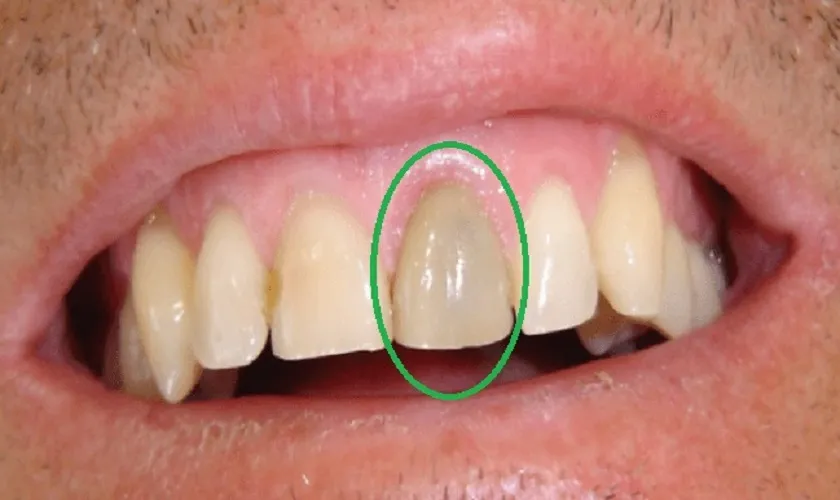

Răng bị đau nhức đến phát sốt, đau đến không còn tập trung được. Đây là lúc bạn cần đến ngay bác sĩ, khả năng cao bạn đã bị viêm tủy răng. Điều trị tuỷ khỏi đau nhức, phục hồi chức năng và giữ răng là việc không thể chậm trễ.

Tuỷ răng có thể bị tổn thương không thể hồi phục do nhiều nguyên nhân

Sự xâm nhập của vi khuẩn (do sâu răng, viêm lợi – viêm nha chu).

Chấn thương (cơ học, nhiệt độ…) khiến răng bạn không ngừng đau buốt, lúc đó răng cần được điều trị tuỷ răng.